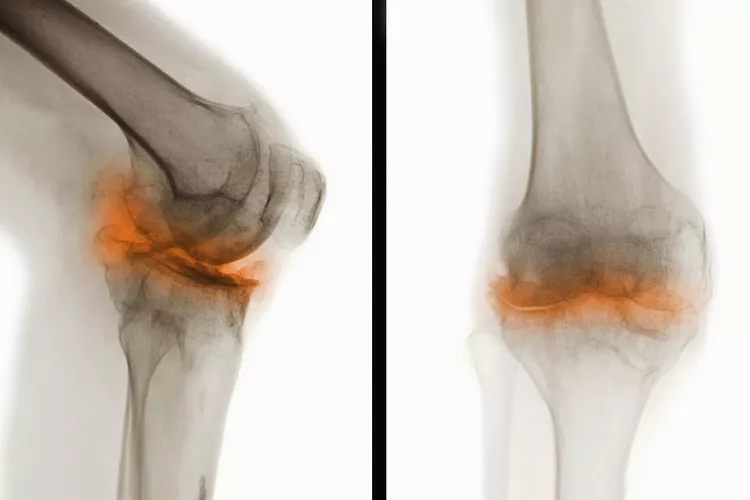

在骨關節炎(OA) 中,覆蓋骨頭末端并幫助骨頭相互滑動的光滑軟骨會逐漸磨損。這會導致骨頭相互摩擦和磨擦。

關節損傷

可能的問題包括:

- 脊柱神經受到擠壓(后天性脊椎滑脫或脊椎狹窄)

- 關節感染,但這種情況很少見

- 關節周圍的肌腱和韌帶變薄或撕裂,導致關節不穩定

- 軟骨溶解癥,軟骨突然完全破裂,導致關節內組織松散

- 應力性骨折,由于反復的壓力而緩慢地在骨頭上形成細微裂縫

- 貝克囊腫是膝蓋后面的軟性充滿液體的腫塊。它們大多無痛,但會壓迫血管導致腿部腫脹,或破裂并引起疼痛